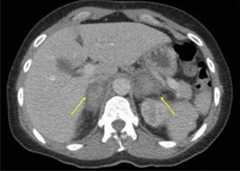

CT of adrenal hemorrhage:

Contrast imaging of the abdomen and pelvis showing bilateral adrenal hemorrhage (yellow arrows) in a patient presenting with sepsis